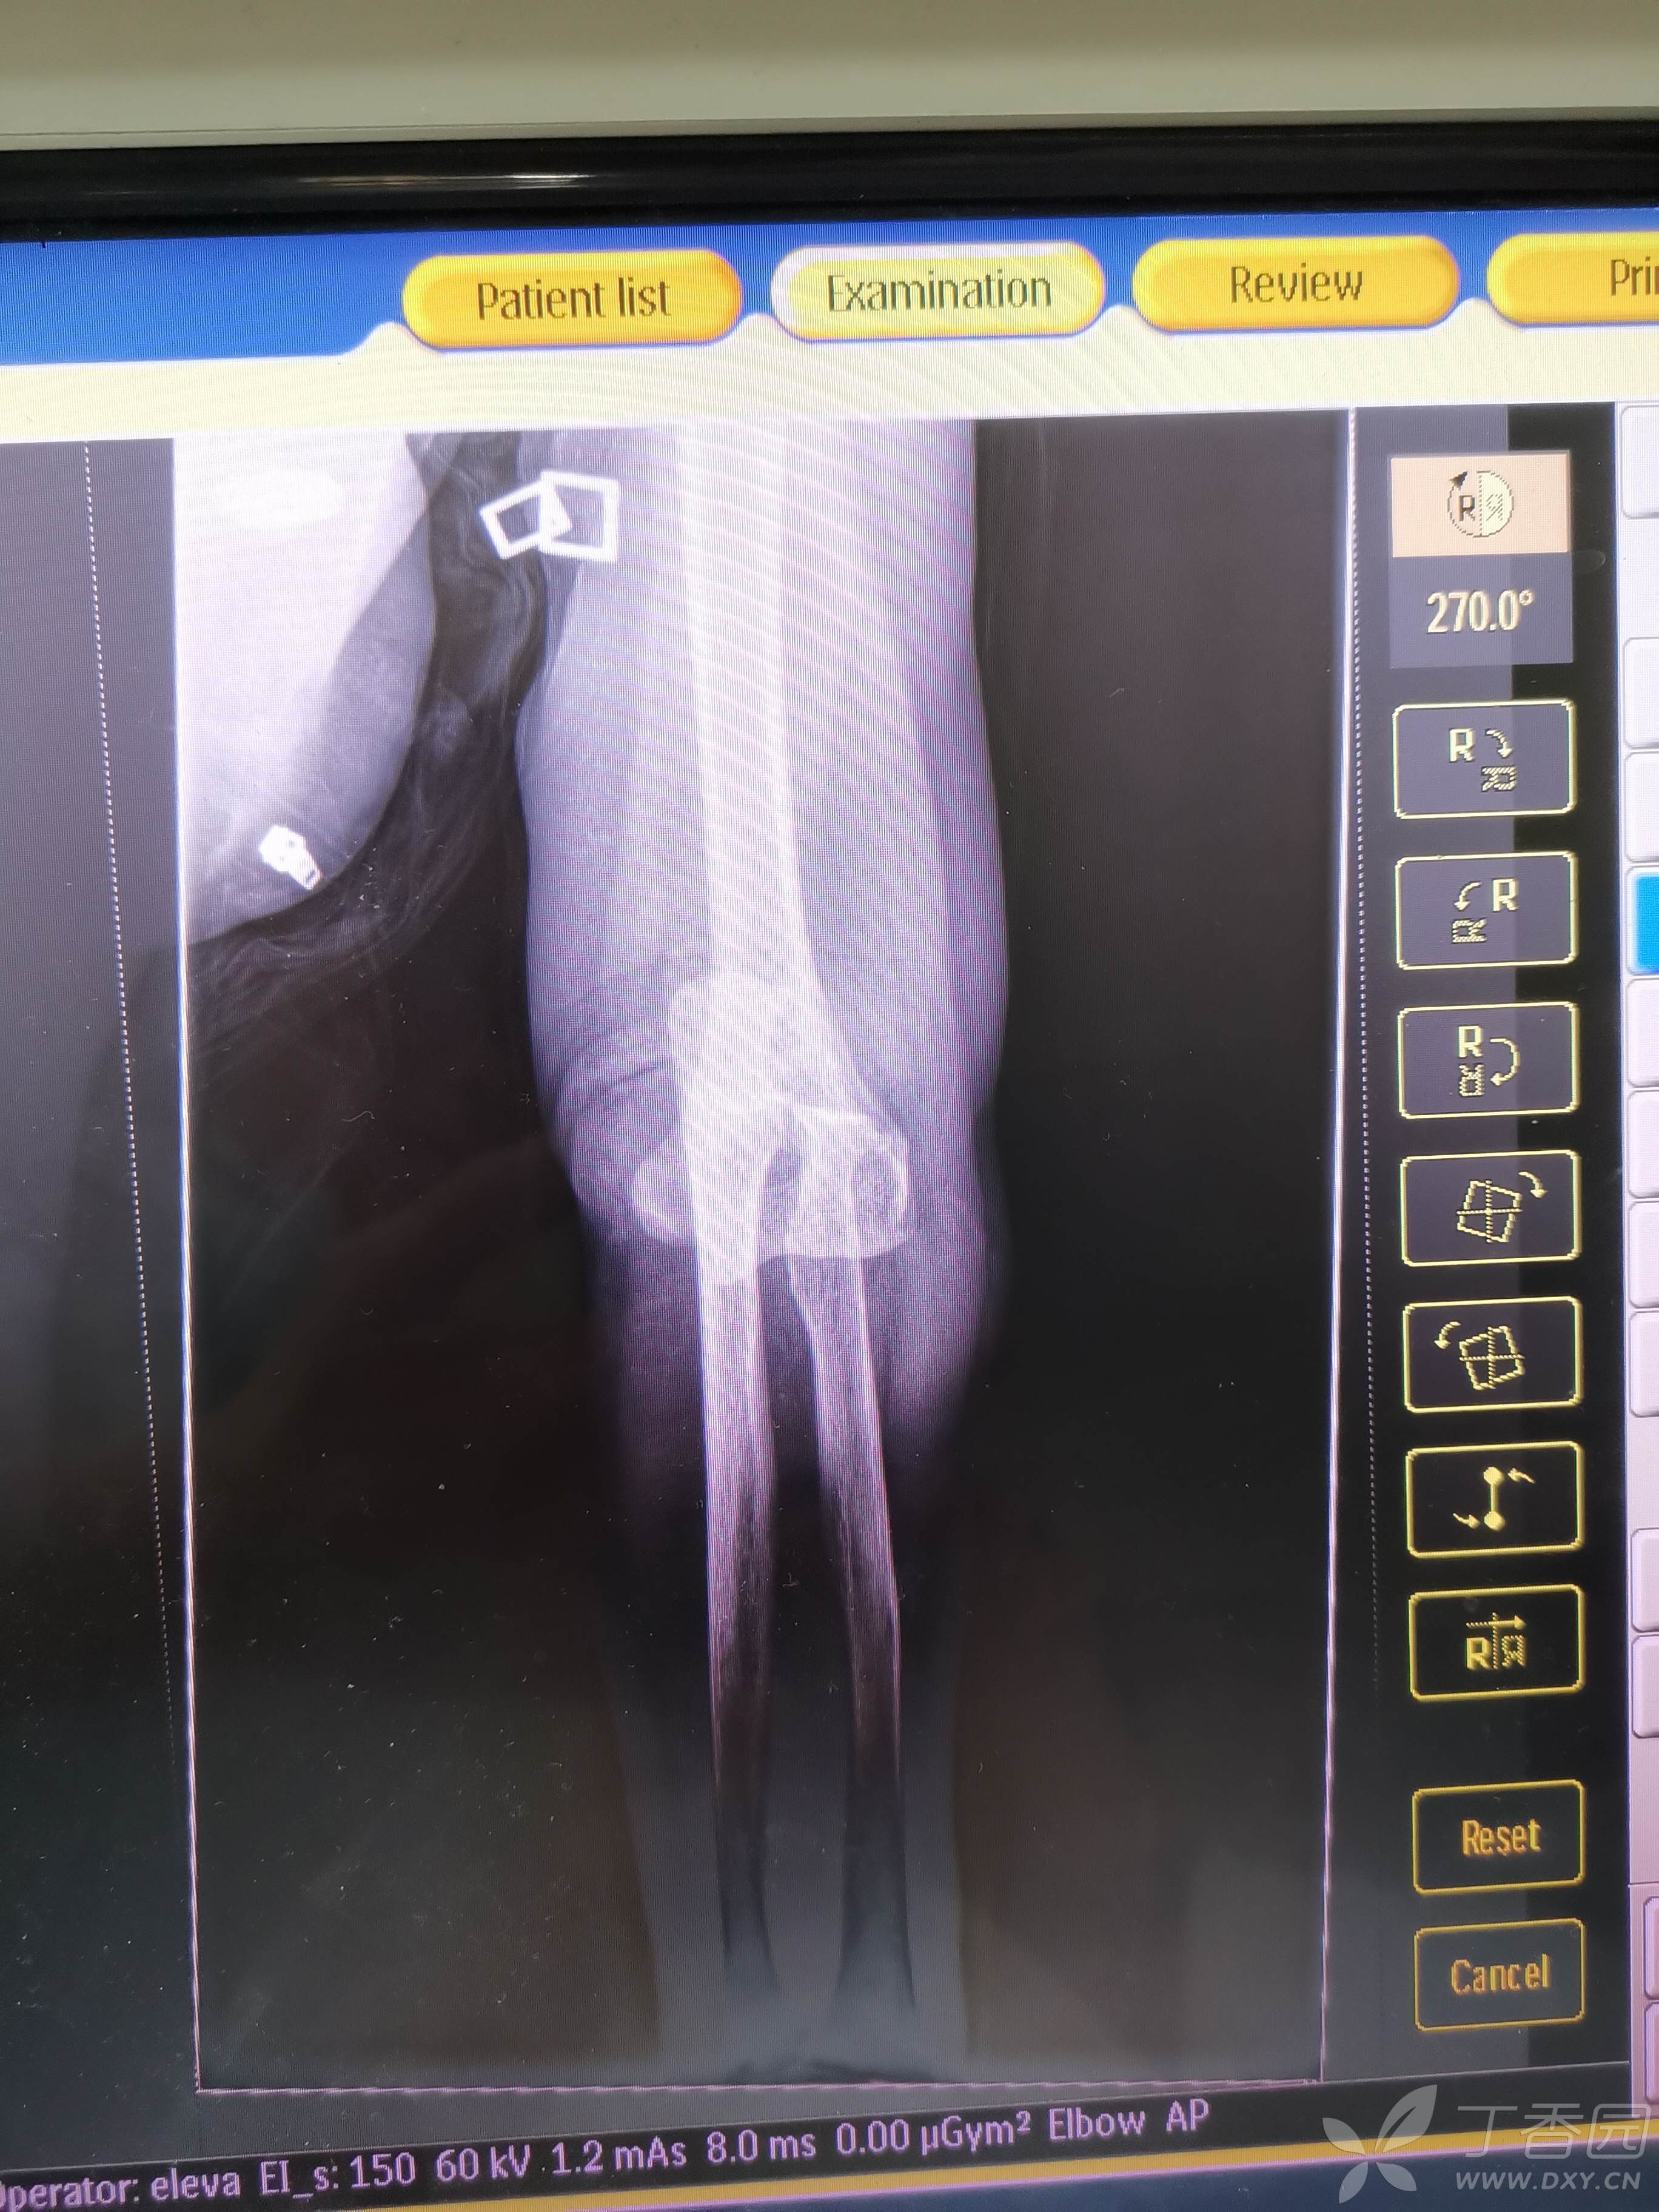

患者女,73岁,摔伤2小时入院

以上为脱位当时

复位后,屈伸活动良好,给予屈曲位石膏固定!但患者可能因为贫困原因,感觉良好,死活不拍复位后片子,强烈要求回家!

对于肘关节脱位,大家有没有好的复位建议,本人当时第一次复位,当时在想复位后如何固定,屈曲位还是伸直位固定,过不过腕关节,中立位还是旋后位固定?